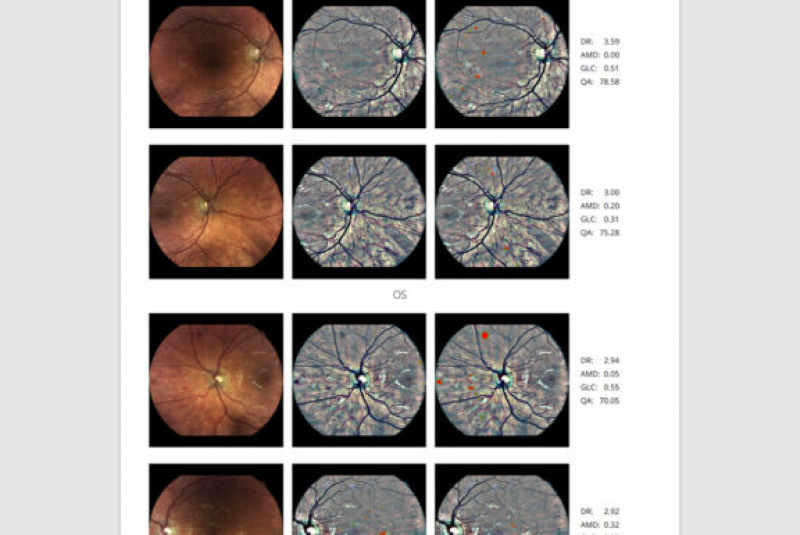

Z vysoko kvalitných fotografií očného pozadia zaobstaraných technológiou iCare DRSplus diagnostikuje diabetickú retinopatiu pomocou umelej inteligencie. Efektívny skríning vyhodnotený softwarom využívajúcim umelú inteligenciu iCare RETCAD®, je schválený pre klinické použitie a je klasifikovaný podľa certifikácie CE (0344) ako zdravotnícky prostiriedok triedy IIa, ktorý šetrí drahocenný čas ako lekára, tak aaj pacienta, umožňuje včasnú intervenciu a pomáha poskytovať včasnú starostlivosť. Analýza pomocou iCare RETCAD® nenahradzuje vyšetrenie zdravotného stavu očí.

Ako funguje ICARE ILLUME

AI (umelá inteligencia) okamžite rozpozná práznaky diabetickej retinopatie a klasifikuje výsledky podľa závažnosti na základe medzinárodných klasifikácií. Získate prehľad s hodnotením závažnosti záchytu, kde po analýze snímok zachytených kamerou iCare DRS Plus je automaticky generovaný report o pacientovi so stupnicou závažnosti pre diabetickú retinopatiu na základe medzinárodných štandardov (ICDR, AREDS).

Fundus kamera iCare DRSplus urobí celkovo 4 vysoko kvalitné True Color snímky (dve z pravého a dve z ľavého oka), ktoré sa automaticky ukladajú na cloud a posielajú sa na spracovanie AI - umelej inteligencii. Report je dostupný ihneď a ten je možné prekonzultovať s pacientom počas tej istej návštevy u lekára.